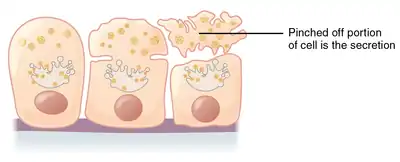

| Apocrine – by membrane budding (loss of cytoplasm) |

Apocrine (/ˈæpəkrɪn/)[1] is a term used to classify the mode of secretion of exocrine glands. In apocrine secretion, secretory cells accumulate material at their apical ends, and this material then buds off from the cells, forming extracellular vesicles. The secretory cells therefore lose part of their cytoplasm in the process of secretion.